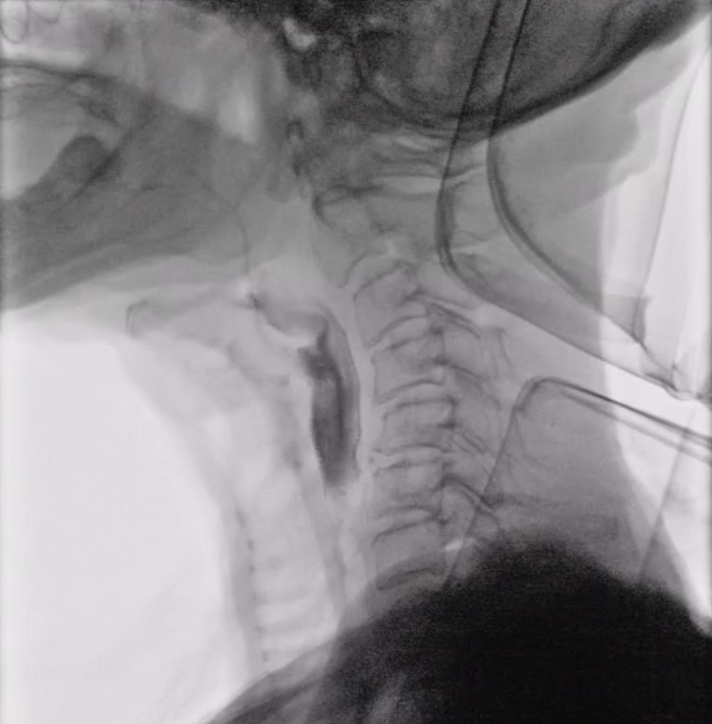

②入院・VF検査(飲み込みのレントゲン検査)

入院初日にVF検査を実施し、嚥下状態を詳しく確認します。